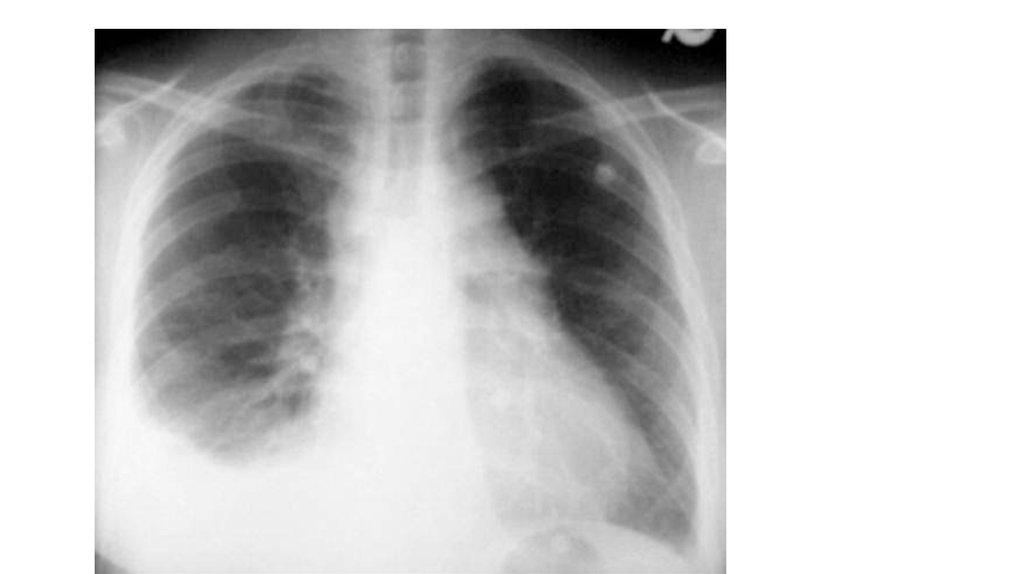

• Рентгенография органов грудной клетки

Высокое стояние купола диафрагмы на стороне поражения,

расширению правых отделов сердца и корней лёгкого, обеднению

сосудистого рисунка, наличию дисковидных ателектазов.

Обнаруживают треугольные тени и жидкость в синусе на стороне

инфаркта. (инфарктная пневмонии)